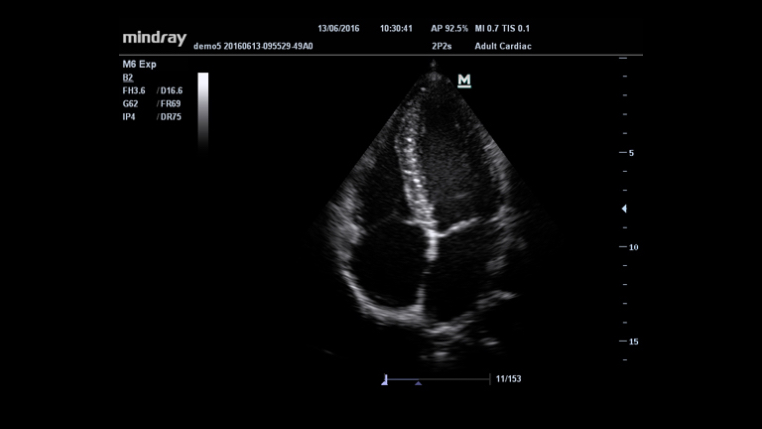

System diagnostyki USG

Specjaliści kliniczni przebyli długą i trudną drogę, aby uzyskać możliwość stosowania diagnostyki obrazowej o wysokim standardzie przy łóżku pacjenta poddawanego intensywnej opiece medycznej. Dotychczas wybór wielkości i wydajności aparatów USG był ograniczony. Mając na względzie dostępność opieki zdrowotnej, Firma Mindray wprowadziła nowy aparat M6, idealnie łączący w sobie możliwości i rozmiar potrzebne do niezawodnego diagnozowania pacjenta przy łóżku.